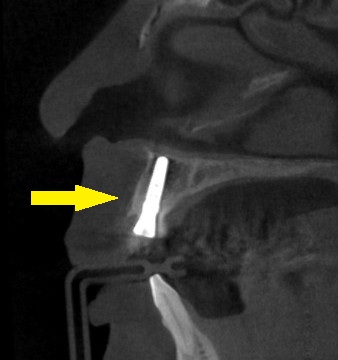

CTを撮影すると、外側、口唇側の骨がとても薄くて、抜歯して治癒を待っていると、その骨が吸収され、外側がかなり凹んでしまうと予測されました。

そこで、外側、口唇側の骨の吸収を防ぐために、歯の口唇側の一部を薄く残して、他の部分を抜歯し、そのままインプラントを埋入するという手術方法を提案させていただきました。

ソケットシールドテクニック、あるいはルートメンブレンテクニックと呼ばれる方法です。

患者様の了承が得られましたので、本日、歯根の一部をシールド状に残して抜歯し、インプラントを埋入、隙間に人工骨を填入しました。

下の写真が手術前後のCTです。